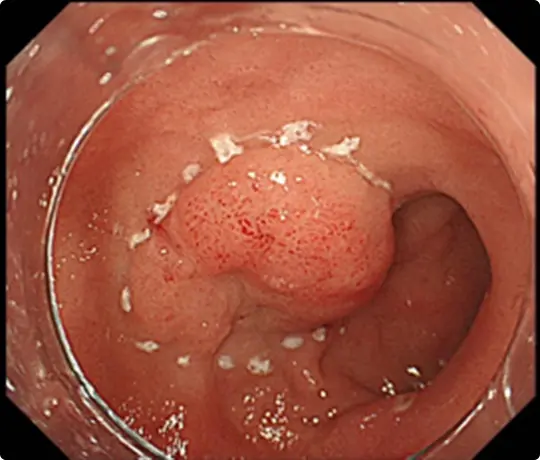

約4cmの高度な線維化を伴う早期大腸がんに対するESDを提示します。当科で考案したUnderwater ESD(生理食塩水の中で行うESD)が有効でした。

重症の潰瘍性大腸炎の既往があり、高度な線維化により難易度が高いと予想されました。

粘膜の下に液体を注入して病変を浮かせます。

病変の外側の粘膜を電気メスで切開したところです。

粘膜の下の組織(粘膜下層)を電気メスで剥がそうとしていますが、高度な線維化で筋層との境界がよく分かりません。このままでは筋層を傷つけて穴をあけてしまうリスクがあります。

当科で考案したUnderwater ESD(生理食塩水の中で行うESD)を行うことで光の反射がなくなり、拡大効果もあるため、鮮明な視野が得られ粘膜下層と筋層の境界が分かりやすくなります。筋層を傷つけないように、精密に剥離することが可能になります。